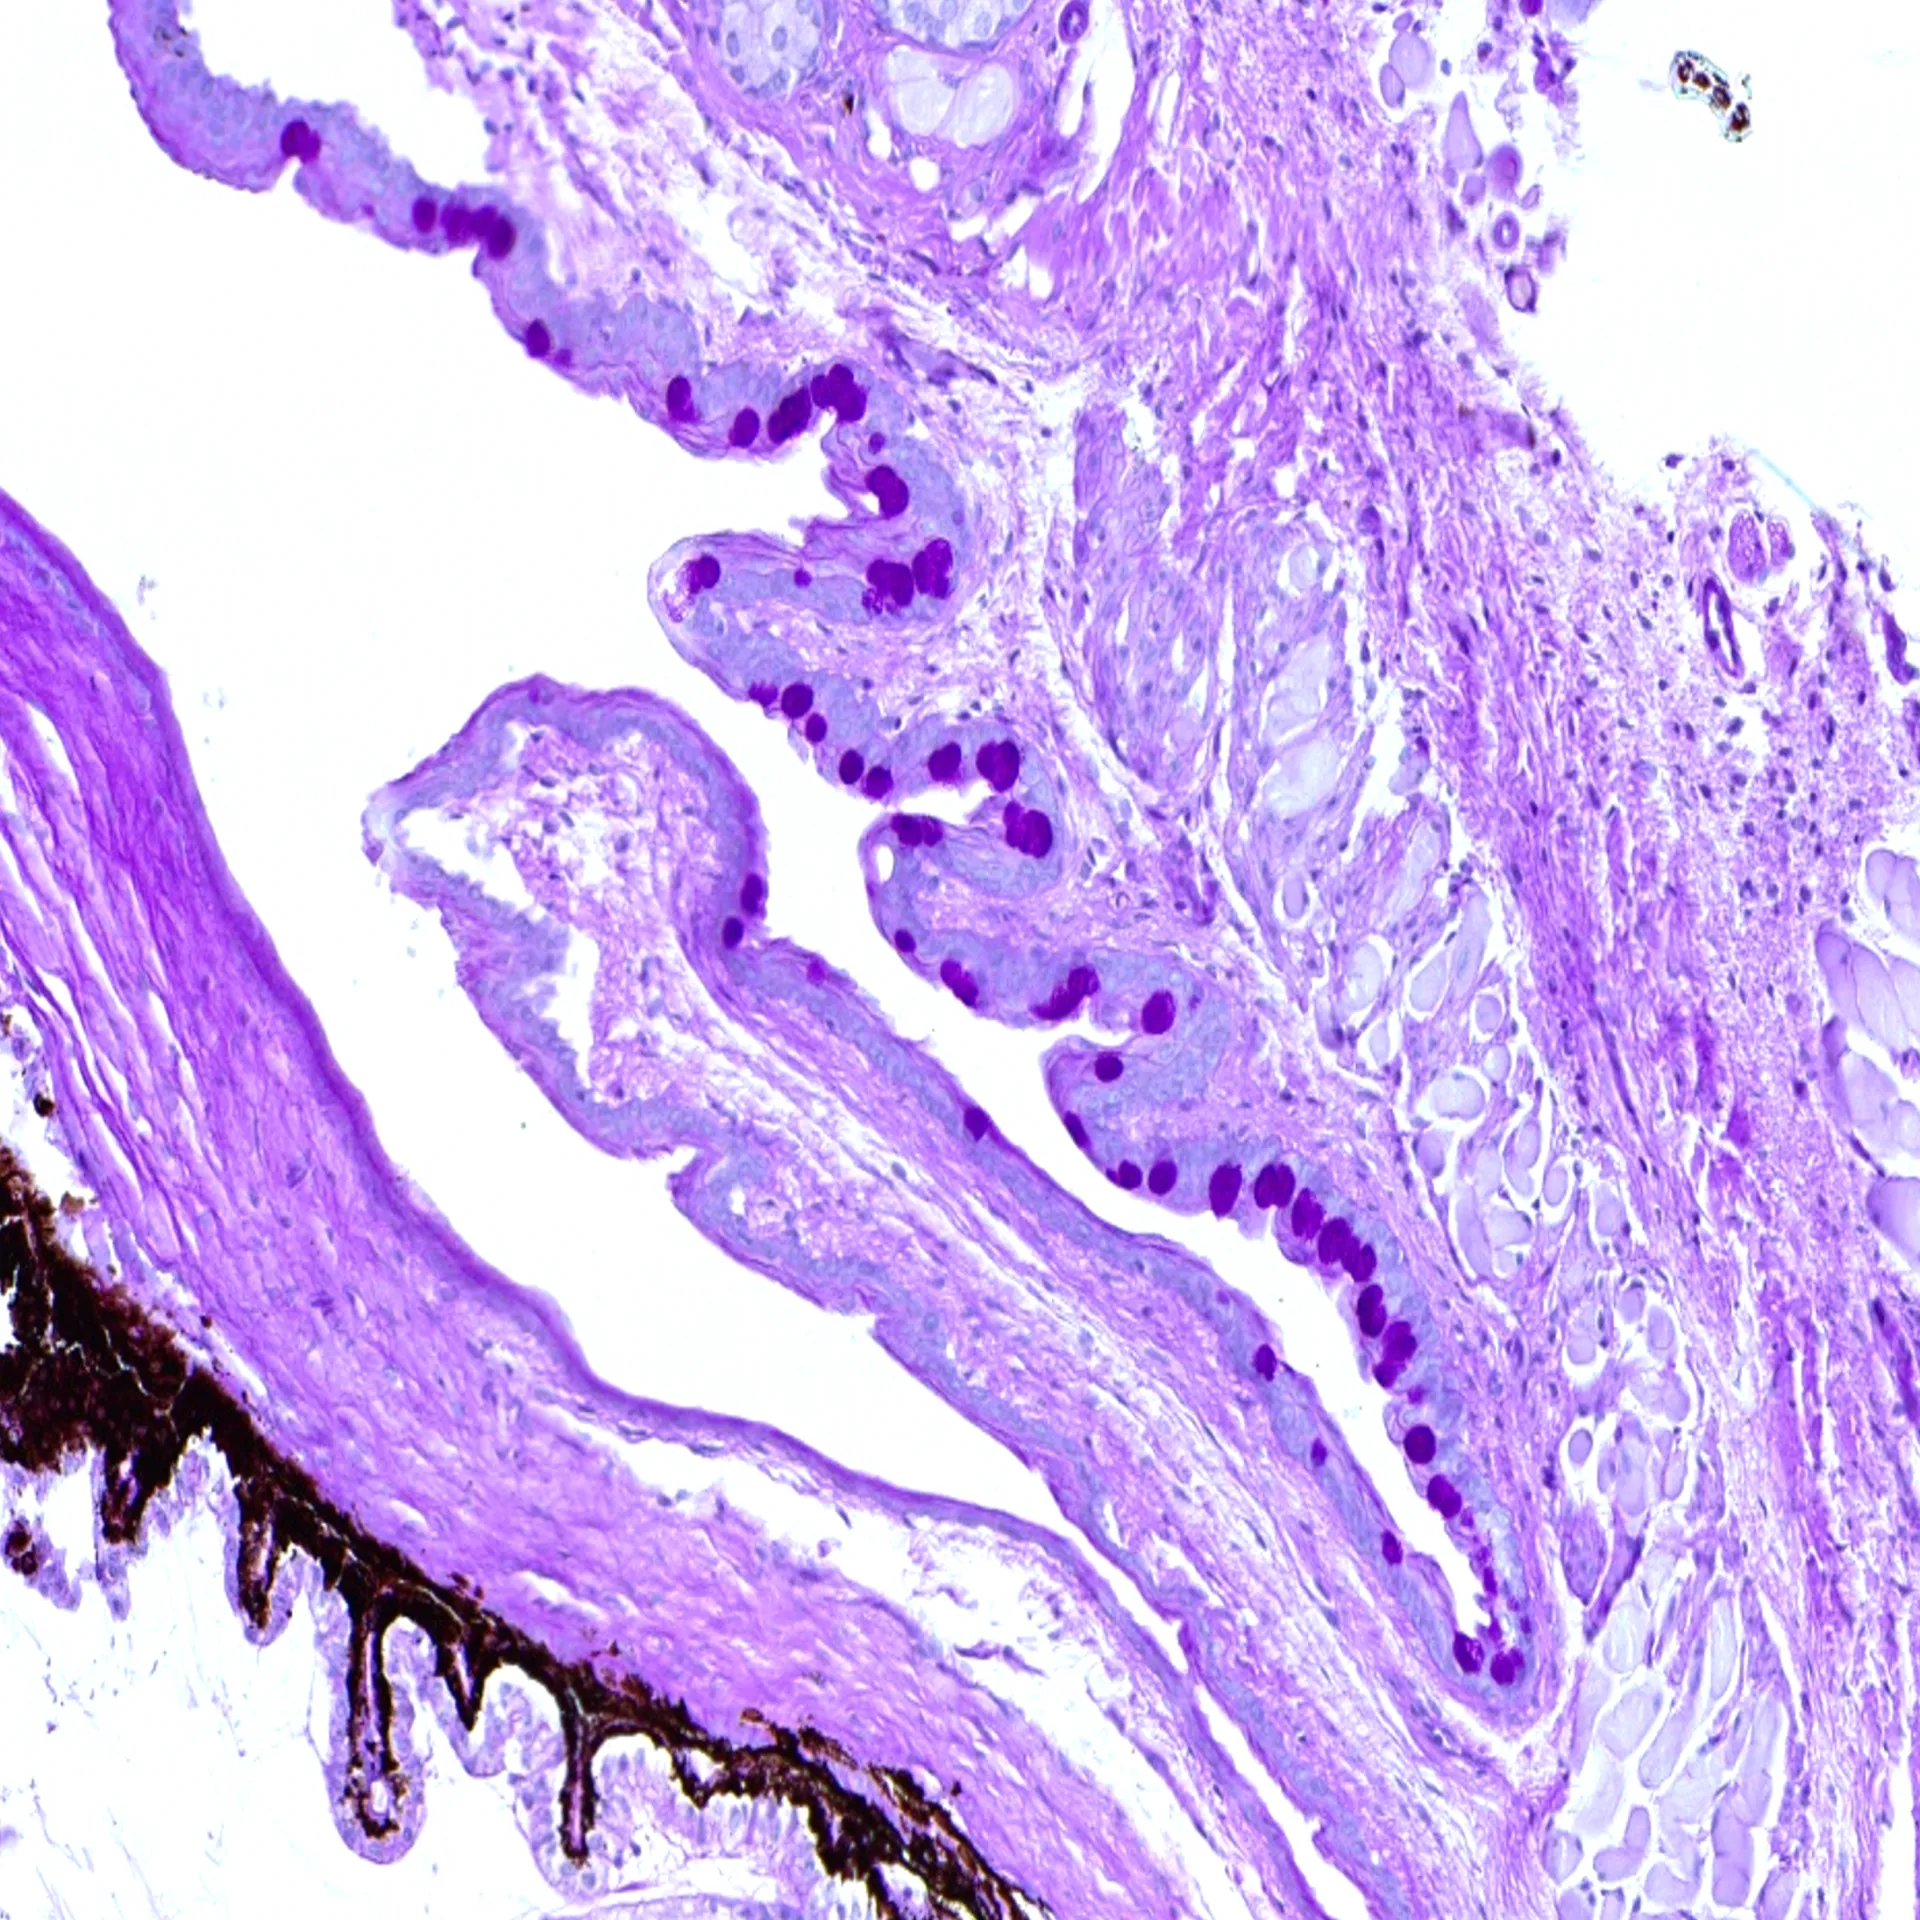

Histological analysis

– Grading of immune cell infiltration in the lacrimal gland

– Quantification of conjunctival goblet cells

– Quantification of corneal thickness

Learn moreHistological staining

Histological staining techniques for ocular and nervous system tissues to support detailed analysis.